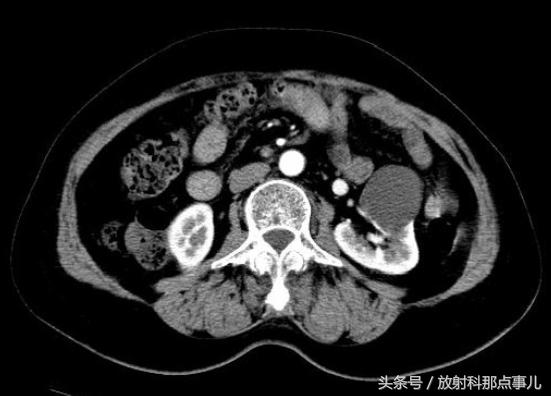

单纯肾囊肿最为常见,约50%的50岁以上的人群会发现单纯肾囊肿。单纯肾囊肿是偶然发现的病变,即使体积较大也不需要随访。

在CT图像上,单纯肾囊肿的密度接近0HU,不含任何强化成分,有一层不易显示的薄壁。